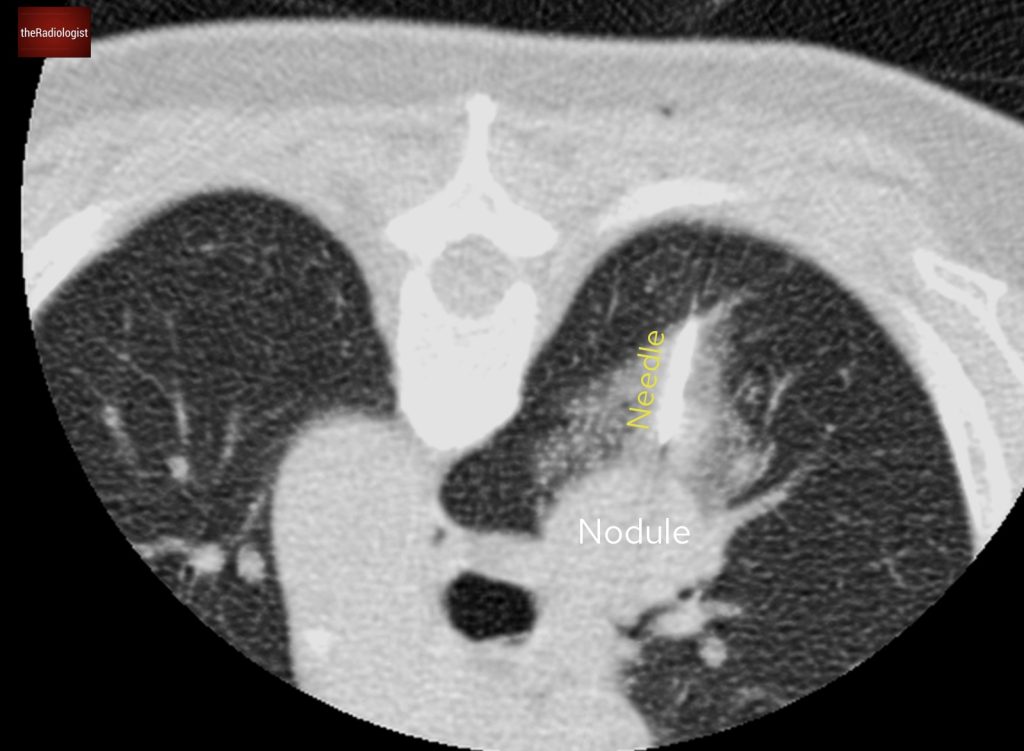

A CT of the thorax, abdomen and pelvis with contrast was performed confirming the X-Ray findings of multiple bilateral well defined lung nodules of different sizes.

CT confirms several well defined nodules within both lungs.

To be certain of the diagnosis a CT-guided lung biopsy was performed which provided the answer: benign metastasising leiomyomas.

CT guided biopsy of a large right sided lung nodule was performed to obtain a tissue diagnosis of benign metastasising leiomyomas.